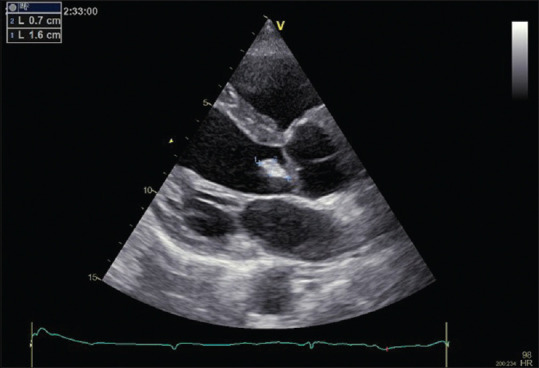

Results: A 55-year-old patient with culture-negative endocarditis was referred to our department for an ocular examination. His visual acuity was 20/20 in both eyes. Fundus examination showed white retinal infiltrates with few superficial retinal hemorrhages scattered in the posterior pole. There was no staining on fluorescein angiography. Swept-source optical coherence tomography (SS-OCT) revealed increased inner retinal reflectivity with a focal area of retinal thickening. Laboratory tests showed a high titer of antibodies against Coxiella burnetii. The patient was treated with doxycycline. Two weeks later, fundus examination showed partial resolution of retinitis with inner retinal thinning in SS-OCT.

Conclusions: Multifocal retinitis is an uncommon presentation of Q fever. The diagnosis should be considered, especially when associated with culture-negative infective endocarditis, highlighting the importance of routine ocular examination.